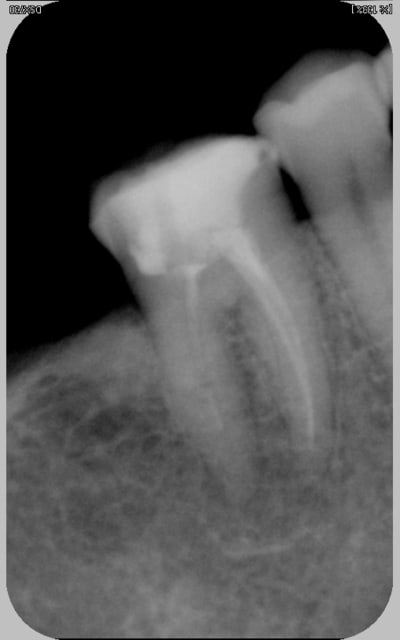

là la dame avait une belle tumefaction ggale et la dent douloureuse a la pression. je fais une radio (comment faire autrement?)

la tumefaction est bien en regard du canal distal qui ne parait pas tip top, pourtant je doute encore car je sais que son prat endodontise bien d'habitude. La dent est restaurée avec un compo collé (mais j'ai pas de photo là, dommage, il était chouette)

l'image radio était trompeuse et le probleme n'était pas endo.